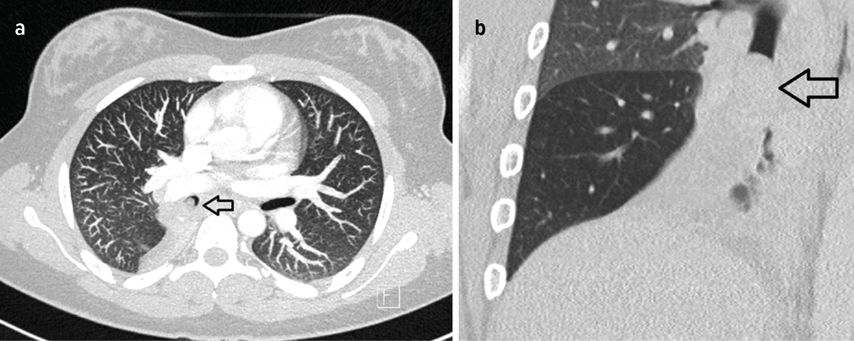

Bei der aktuellen Vorstellung wurde eine intravenöse antibiotische Behandlung initiiert, daraufhin sistierten die Hämoptysen. Thoraxsonografisch zeigte sich aber eine Persistenz der Unterlappenatelektase. In der daraufhin durchgeführten CT-Thoraxaufnahme ergab sich der Verdacht auf einen Komplettverschluss des distalen Anteils des rechten Bronchus intermedius (Abb. 2). Zur weiteren Abklärung des Befunds wurde eine flexible Bronchoskopie durchgeführt, hier zeigte sich der Befund einer endobronchialen Raumforderung (Abb. 3) mit Komplettverlegung des Bronchus, zudem waren in der endobronchialen Ultraschalluntersuchung (EBUS) suspekte Lymphknoten zu erkennen. In der gleichen Sitzung wurden aus Tumor und Lymphknoten Biopsien entnommen.

Abb. 2: a: CT-Thorax, Transversalschnitt, Tumor mit Pfeil markiert, b: CT-Thorax, Frontalschnitt, Tumor mit Pfeil markiert (rechte Lunge)